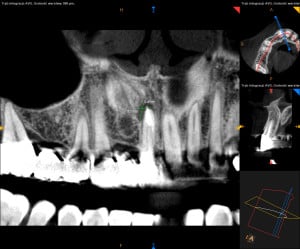

Dokumentacja RTG

- OPG przed zabiegiem wykonane przez lekarza prowadzącego

- RVG

- CBCT przed i po zabiegu